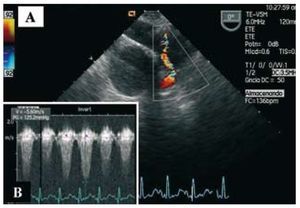

The patient came to the emergency room with a persistent fever of 20 days' duration, associated over the past 5 days with dyspnea and fatigue on minimum minimal exertion. He was admitted to the cardiology department; serial blood cultures isolated Streptococcus viridans. Transesophageal echocardiography showed a mildly dysfunctional dilated right ventricle, with a round, slightly mobile image on the pulmonary trunk (homograft), indicative of an endocarditis vegetation that considerably increased the pre-existing stenosis (Figure 1A); the maximum transpulmonary gradient was 125 mm Hg (Figure 1B). Magnetic resonance imaging was performed to provide better anatomic definition and tissue characterization of the homograft and lesion (Figure 2, arrow).

Figure 1.